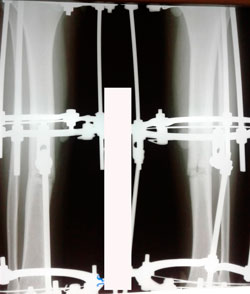

в процессе

Вложения

image-25-08-20-12-19-1.jpg